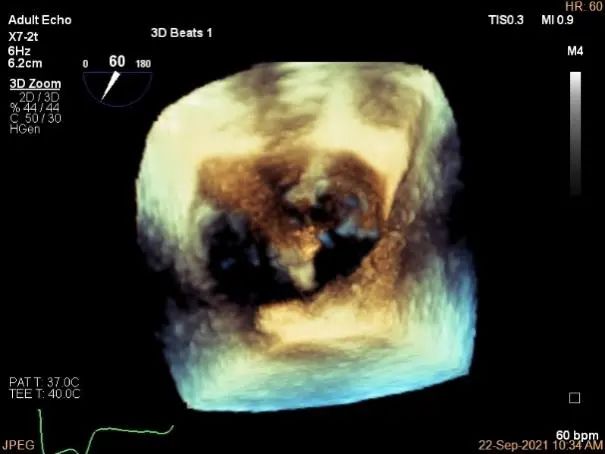

术中超声

P2区脱垂,宽14.8mm,Gap:3.3mm

3D-color,返流重度,3+级

三维评估两个夹子位置

3D-color再次确定未见残余分流